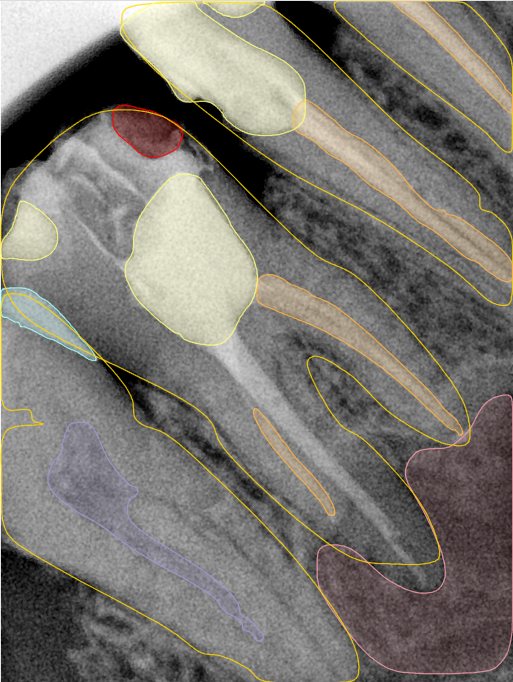

CR/DR 牙齿分割阶段记录

当前进展

- 完成了 CR/DR 牙齿相关分割训练

- 当前结果已经达到阶段预期,但仍有细节问题需要继续处理

相关测试

遇到的问题

- 训练过程中出现过 mask 下移问题

- 部分结果会出现 box 填充异常

- mask 边缘仍然有比较明显的锯齿感